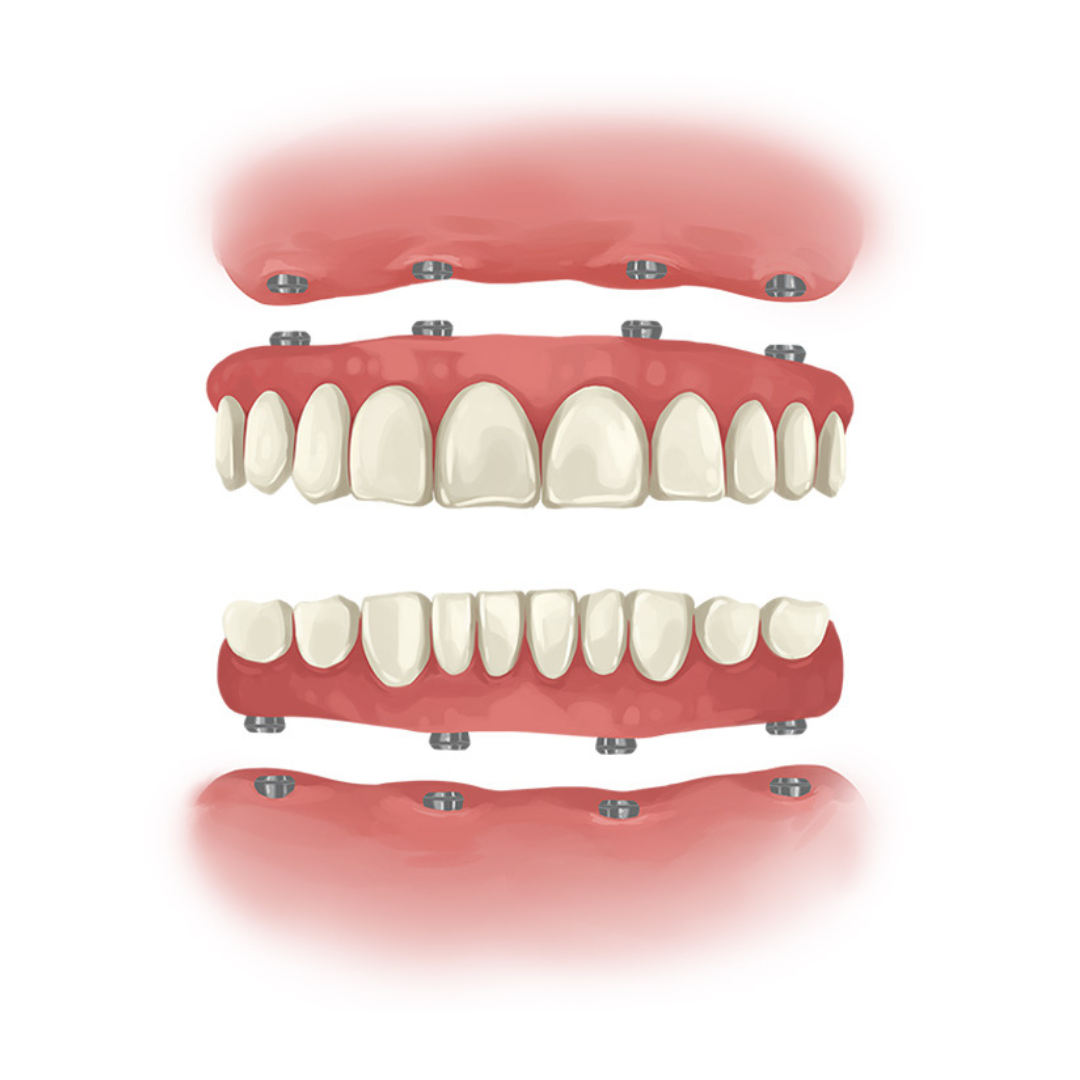

The All-On-4 protocol is an advanced dental implant technique designed to provide a full-arch restoration using only four implants. This method is particularly beneficial for patients with significant tooth loss and minimal bone density.

The procedure involves strategically placing two anterior implants vertically and two posterior implants at an angle, optimizing the use of available bone and providing maximum support for the dental prosthesis.

One of the main advantages of the All-On-4 protocol is its ability to avoid the need for bone grafting, which can be a lengthy and invasive process. By angling the posterior implants, the technique ensures greater stability and load distribution, allowing for immediate loading of the prosthetic teeth. This means patients can leave the dental office with a functional set of teeth on the same day as the surgery.

The All-On-4 protocol offers a cost-effective, efficient, and reliable solution for full-mouth rehabilitation, making it a popular choice for many dental patients.